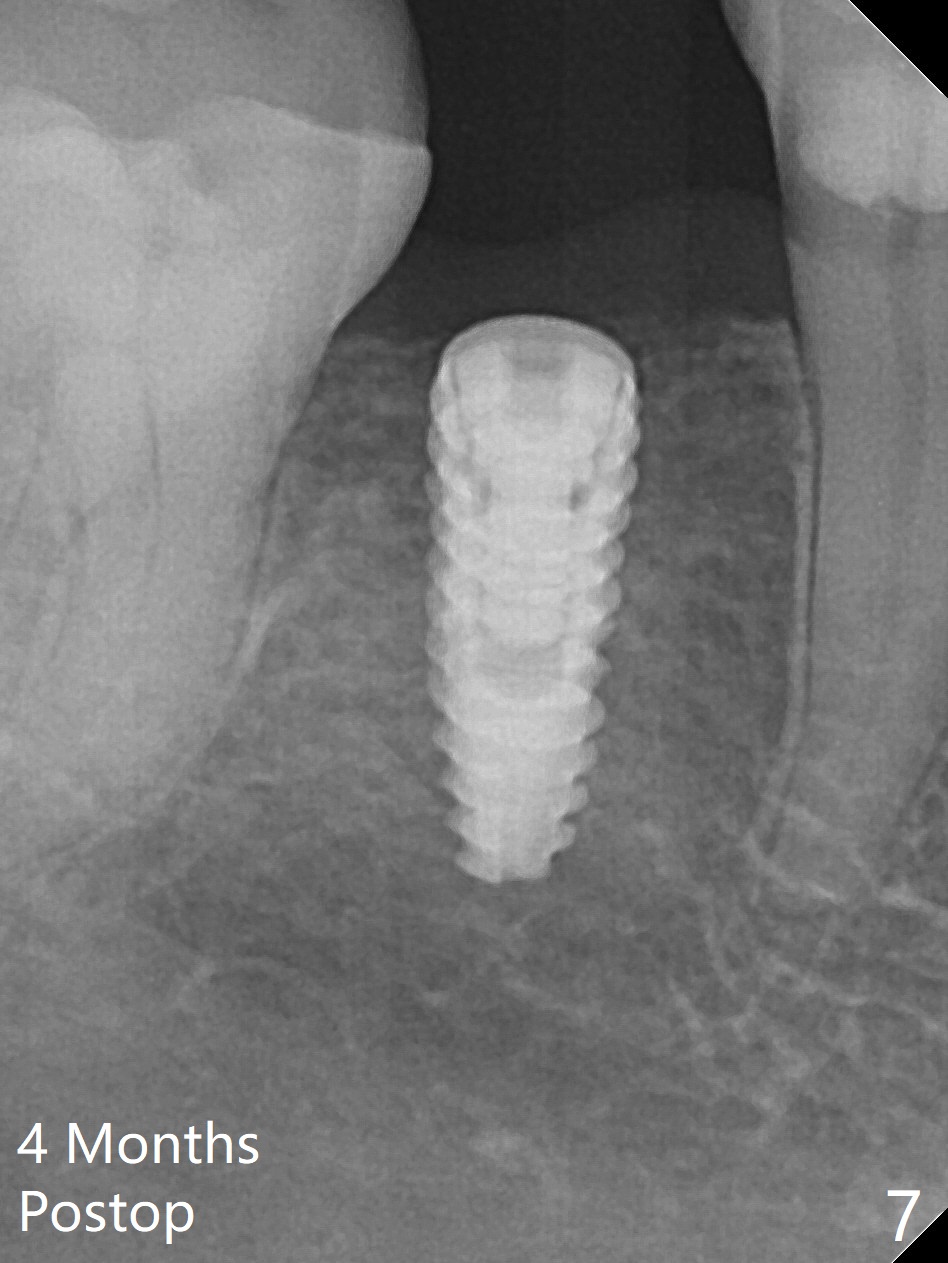

After incision the ridge at #29 is not so narrow as shown in Fig.1. But it is still intact, in contrast to what CBCT shows. Osteotomy is initiated with 1.2 mm drill, followed by 1/1.6, 1.3/2.3 and 1.7/3.1 mm DIO Bone Expanders. In fact mesial and distal crestal slots (BEB: bone expansion and bending) are created by using surgical fissure bur in order to insert the last bone expander in place (10 mm, Fig.2). Following 3.5 mm Cortical Tap, a 3.5x10 mm IS Implant is placed ~ 50 Ncm with clearance from the Mental Loop (Fig.3,4 red dashed line) and slightly subcrestal (Fig.5). The most distal part of the distal slot created for BEB is shown in Fig.5 *. Bone resorption is minimal 4 months postop (Fig.6,7). The implant was apparently placed in the middle buccolingually (Fig.8).